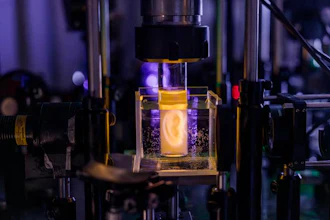

As the design evolves, prototyping is critical in refining implantable devices to ensure they meet safety and performance standards, especially when evolving from preclinical to clinical-grade devices. Promex's expertise in developing custom manufacturing processes allowed for precise control over the device's quality during prototyping.

- Testing for Safety and Efficacy: Implantable devices must undergo rigorous testing to ensure patient safety. Injectsense's preclinical device was first tested in rabbits at a major eye institute in Baltimore, where it demonstrated no adverse effects such as infection or inflammation. Following this, we produced a human-grade device that could be used in human studies. These studies were critical for establishing the safety and efficacy of the device in real-world conditions. Injectsense also utilizes accelerated aging tests to predict the long-term reliability of the sensor, assessing its functionality and stability over time in simulated human conditions.